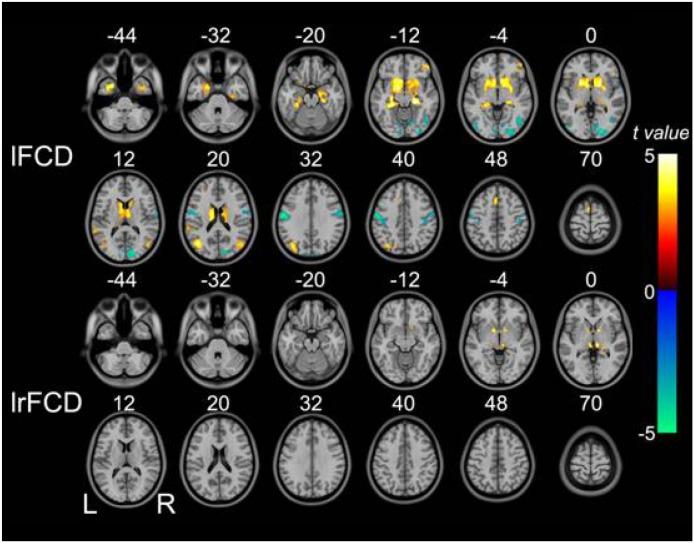

Schizophrenia is a disorder of brain dysconnectivity, and both the connection strength and connection number are disrupted in patients with schizophrenia. The functional connectivity density (FCD) can reflect alterations in the connection number. Alterations in the global FCD (gFCD) in schizophrenia were previously demonstrated; however, alterations in two other indices of the pathological characteristics of the brain, local FCD (lFCD) and long-range FCD (lrFCD), have not been revealed. To investigate lFCD and lrFCD alterations in patients with schizophrenia, 95 patients and 93 matched healthy controls were examined using structural and resting-state functional magnetic resonance imaging scanning. lFCD and lrFCD were measured using FCD mapping, and differences were identified using a two-sample t-test in a voxel-wise manner, with age and gender considered to increase variability. Multiple comparisons were performed using a false discovery rate method with a corrected threshold of P<0.05. Our analysis showed that lFCD was primarily decreased in the postcentral gyrus, right calcarine sulcus, and inferior occipital gyrus lobule, but increased in the bilateral subcortical regions. The differences in lFCD were more pronounced and complicated than those in lrFCD. In summary, in contrast with previous studies that focused on the connection strength, our findings, from the perspective of connection number, indicate that schizophrenia is a disorder of brain dysconnectivity, particularly affecting the local functional connectivity network, and support the hypothesis that schizophrenia is associated with a widespread cortical functional connectivity/activity deficit, with hyper- and/or hypo-connectivity/activity coexisting in some cortical or subcortical regions.

精神分裂症是一种大脑连接功能障碍性疾病,精神分裂症患者的连接强度和连接数量均受到破坏。功能连接密度(FCD)可以反映连接数量的改变。先前已证实精神分裂症患者的全脑功能连接密度(gFCD)存在改变;然而,大脑病理特征的另外两个指标,即局部功能连接密度(lFCD)和长程功能连接密度(lrFCD)的改变尚未被揭示。为了研究精神分裂症患者的lFCD和lrFCD改变,我们使用结构和静息态功能磁共振成像扫描对95例患者和93例匹配的健康对照进行了检查。使用FCD图谱测量lFCD和lrFCD,并采用双样本t检验以体素为单位识别差异,同时考虑年龄和性别以增加变异性。使用错误发现率方法进行多重比较,校正后的阈值为P<0.05。我们的分析表明,lFCD主要在中央后回、右侧距状沟和枕下回小叶降低,但在双侧皮质下区域增加。lFCD的差异比lrFCD更明显和复杂。总之,与以往关注连接强度的研究不同,我们从连接数量的角度发现,精神分裂症是一种大脑连接功能障碍性疾病,尤其影响局部功能连接网络,并支持精神分裂症与广泛的皮质功能连接/活动缺陷相关的假说,在一些皮质或皮质下区域存在连接增强和/或减弱以及活动增强和/或减弱并存的情况。